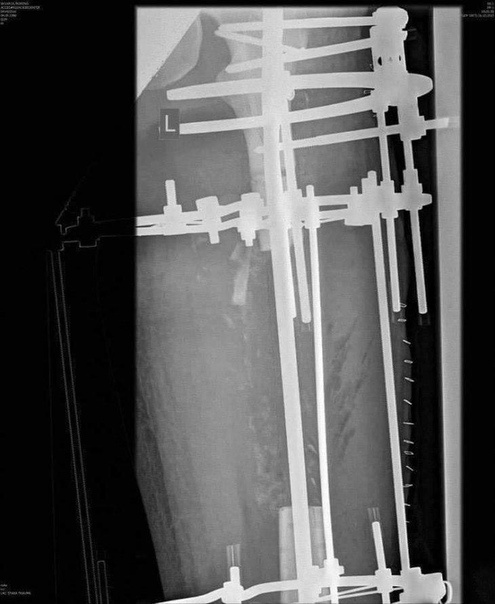

После ДТП мужчина решил сделать из своей бедренной кости, а точнее из ее осколков, рукоятку ножа.

После ДТП мужчина решил сделать из своей бедренной кости, а точнее из ее осколков, рукоятку ножа.  Довольно крепкая психика.